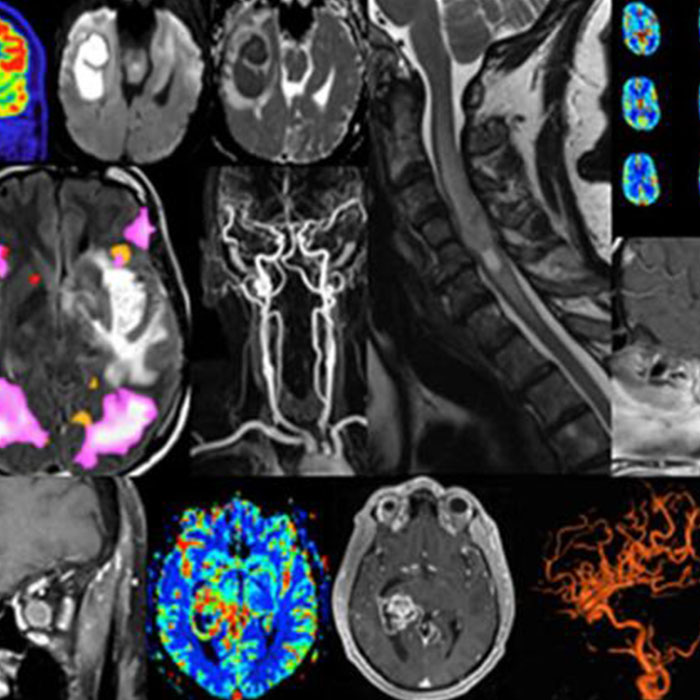

Nöroradyoloji, radyolojinin bir yan dalı olarak kabul edilmektedir. Temel olarak ana görevi; beyin, omurilik, baş ve boyun bölgesindeki hastalıklarda çeşitli görüntüleme yöntemlerinin kullanılarak tanı konulmasıdır. Bir bilim dalı olarak çeşitli teknik ve disiplinlere sahip olan nöroradyoloji ile yapılacak kontrollerde farklı cihazlar ve teknikler kullanılmaktadır. Radyoloji bölümünde kullanılabilen tüm görüntüleme yöntemleri nöroradyolojide de kullanılabilmektedir. Bu bakımdan hastanın mevcut durumu, yapılmak istenen işlem ve hangi konuda kontrol gerekiyorsa uzman hekimler tarafından doğru ekipmanlar kullanılarak nöroradyoloji kapsamında destek sağlanmaktadır. Mevcut yöntem ve cihazlar arasında, manyetik rönesans, bilgisayarlı tomografi, PET taraması gibi görüntüleme yöntemleri yer almaktadır.

Nöroradyoloji desteği alınması gerektiğinde pek çok farklı test ve tedaviler uygulanabilmektedir. En yaygın olanlarından birisi se röntgen ve ultrasondur. Daha ileri düzeyde tanı ve teşhis gerektiği durumlarda ise bilgisayarlı tomografi olarak adlandırılan BT ve MRG’de tercih edilebilmektedir. Bu açıdan farklı cihazlardan ve yöntemlerden yardım alınması gerekebilmektedir. Nöroradyoloji konusunda destek almak isteyen hastaların, bu konuda tüm imkanları sunan sağlık kurumlarını tercih etmesi oldukça önemlidir. Böylece mevcut rahatsızlık teşhisi için en uygun cihazlar kullanılarak herhangi bir hataya yer verilmeden hastalık sürece devam ettirilebilir. Hangi yöntem ve cihaz tercih edilirse edilsin dakikalar içerisinde hastaların tetkikleri yapılabilmektedir. Nöroradyoloji cihazları, teşhis konusunda çok daha yüksek doğruluk ile çalıştığından dolayı uzmanların işleri daha da kolay hale gelmektir. Çok geniş alanları tarama imkanı sunan cihazlar, böylece kapsamlı bir şekilde kontrol yapılmasını sağlamaktadır.